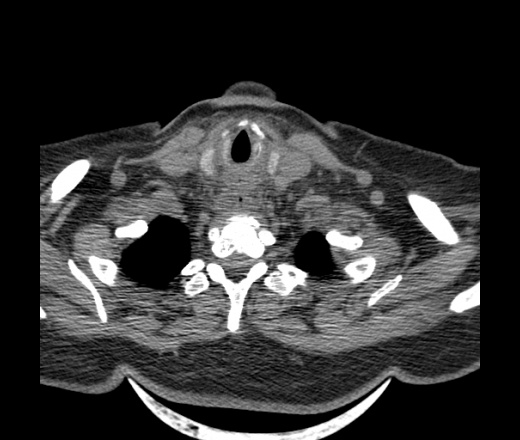

Женщина поступила в х/о спустя 4 дня после того как при употреблении карася подавилась костью.

Наличие газа в средостении на протяжении тел С2-С6 (медиастинальна эмфизема); рыбная кость на уровне тела С6.

При всем уважении, но говорить о медиастинальной эмфиземе, оценивая мягкие ткани шеи, как-то слишком резко. На мой взгляд, это ретрофарингеальное пространство.

Эвакуировали почти 100мл гноя. Но кость не смогли найти. Думаю что она даст дальнейшее ослоднение. Эндоскопически за черпалонадгортаной звязкой не смогли зайти в пищевод, все мягкие ткани отечные, просвет пищевода сдавлен. По всей видимости параэзофагеальная клетчака тоже задействована. Эмпиема, если ее можно так назвать, незнаю как правильно дошла до уровня яремной вырезки. Чем закончиться напишу. Ждем медиастинита.

Флегмона заглоточного пространства шеи, только операция, флегмоны вскрывают. Риск медиастинита.

Согласен с Вами; конечно, наличие газа в клетчатке ретрофарингеального пространства (затмение с опечаткой..). К сожалению, процесс "продвигается" к медиастиниту. Но почему никто, не отмечает наличие рыб. кости; или это для Всех очевидно?

Кость то мы сразу выявили, размеры где то 17*2мм, но ее так и не получается найти в этой каше